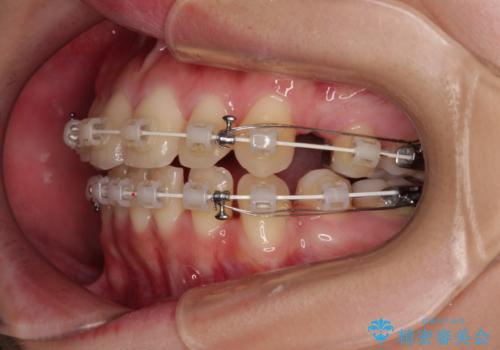

前歯のデコボコを抜歯矯正でスッキリした口元に

- 八重歯やクロスバイトを気にして来院された患者様です。

口元の突出感はありませんでしたが、デコボコが強く、非抜歯矯正とすると出っ歯仕上がりとなる可能性があったため、上下左右の第一小臼歯4本を抜歯し、ワイヤー装置にて矯正治療を行うこととしました。

デコボコがスッキリするだけでなく、口元の突出感も少し改善され、満足のいく仕上がりとなりました。